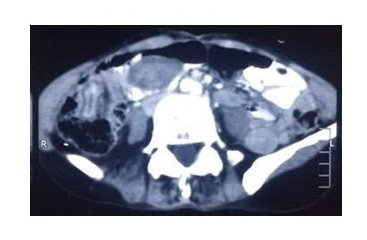

Adult intussusception is an uncommon cause of intestinal obstruction, accounting for less than 5% of cases. Unlike pediatric cases, adult intussusception is usually associated with an identifiable pathological lead point. Trans-anal protrusion of intussusception (TAPI) is exceptionally rare in adults and may mimic rectal prolapse, leading to delayed diagnosis. Inflammatory fibroid polyp (IFP) is a rare benign gastrointestinal lesion and an unusual cause of small bowel intussusception.     A 50-year-old woman presented with a cyanosed pedunculated mass protruding through the anus for three hours, along with a one-month history of hypogastric pain, nausea, vomiting, and weight loss. She had recently been diagnosed with pulmonary tuberculosis and was receiving anti-tuberculous therapy. Laboratory tests revealed leukocytosis and anemia. Ultrasonography suggested intestinal obstruction, while contrast-enhanced CT showed a target sign in the right lower abdomen consistent with ileoileal intussusception. The patient underwent urgent exploratory laparotomy with reduction of the intussusception followed by right hemicolectomy due to suspected malignancy. Histopathology confirmed a 5.7-cm inflammatory fibroid polyp of the ileum with reactive lymphadenopathy. The postoperative course was uneventful, and the patient recovered well at three-month follow-up.     Transanal protrusion of adult ileoileal intussusception secondary to inflammatory fibroid polyp is an extremely rare surgical emergency. Early recognition, appropriate imaging, and prompt surgical management are essential for favorable outcomes.